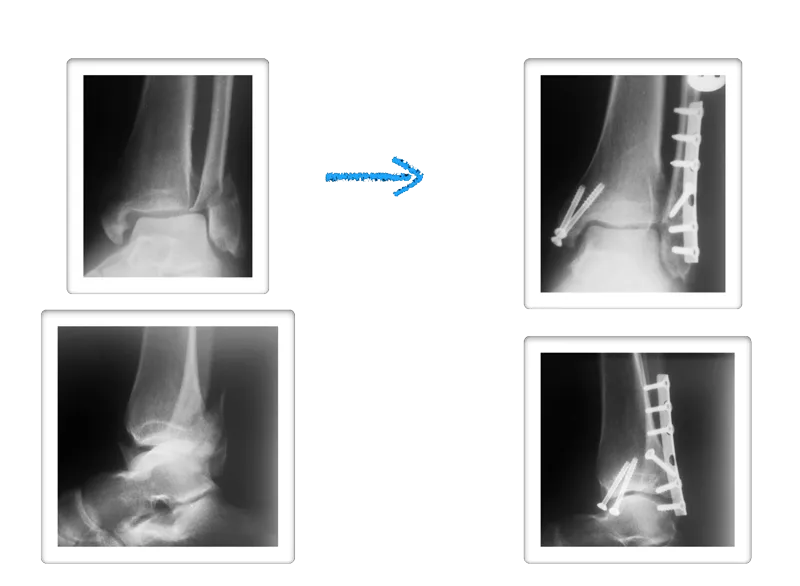

A 32-year-old male patient suffered from a bimalleolar fracture of the ...

Bimalleolar Fracture | PPTX

Bimalleolar Fractures: Management and Evaluation of Treatment ...

Radiology case: Bimalleolar ankle fracture

[PDF] Functional Outcome of Bimalleolar Ankle Fractures Treated With ...